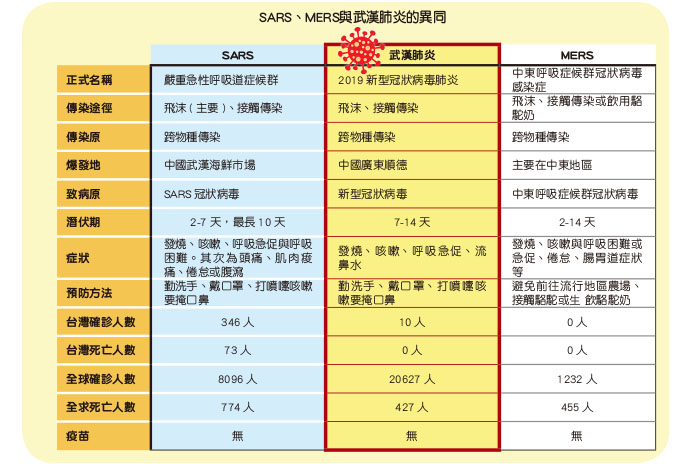

截至2020年2月4日,發布的最新疫情動態,統計資料顯示中國已確診共20462例,死亡426例;世界疫情分布則以泰國19例、日本20例、新加坡18例、南韓16例較為嚴重,臺灣也有10例確診,其中飛律賓已有1例死亡。這樣驚人的數據和傳播速度,很難不讓人聯想到2002年所爆發的SARS疫情,究竟武漢病毒和SARS有何不同,本刊將帶您一窺究竟。

姑且不論這些陰謀論的真實性為何,武漢肺炎的模式和17年前SARS瘟疫驚人的相似,染病的野生動物在傳統市場上販售,未明的病毒跨物種殺進人間。2003年,SARS這個浩劫讓和平醫院封院,7名醫護人員殉職,台灣共有346名確診病例,造成73人死亡;而在全球,則是有8,096名病例,774人死亡。而如今2019新型冠狀病毒肺炎疫情仍舊在瘋狂的肆虐著,更可怕的是到目前為止,尚未有疫苗能治癒,只能依靠支持性治療。究竟SARS與武漢肺炎和MERS有哪些異同呢?我們從上表就能看出一些端倪。